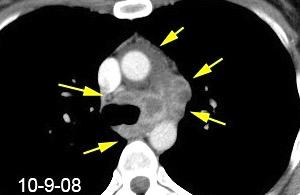

99.GANGLIOS CON HIPERCAPTACIÓN TRAS

CONTRASTE

Ca. Papilar de tiroides. Hipernefroma. Estómago

Ca. microcítico de pulmón

Melanoma

Ca. gástrico

Cabral FC et al. Hypervascular mediastinal masses: Action points for radiologists. Eur J Radiol 2015